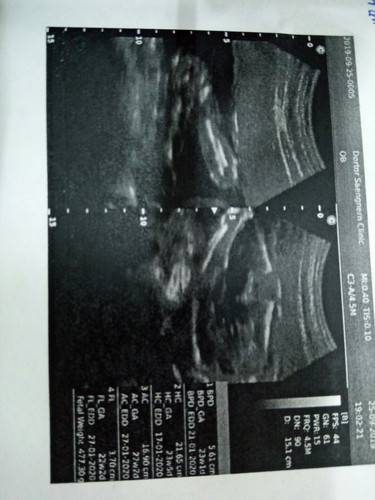

ตอนดูกะหมอหมอว่าผู้หญิงค่ะ..แม่ๆท่านไหนดูออกดูตรงไหนค๊ะ...

ตอนหมอซาว...ในจอมันชัดค่ะ..เห็นแขนเห็นขาชัดเลย..แต่ตรงเพศนี้มองไม่ออก...แต่หมอบอกผู้หญิงก้ผู้หญิงและมาง...555

ปกติตอนดูหมอจะบอกว่า อันนี้คืออะไร ตรงนี้คืออะไรประมาณนี้ค่ะ มาดูเองก็ งงๆเหมือนกัน 😁